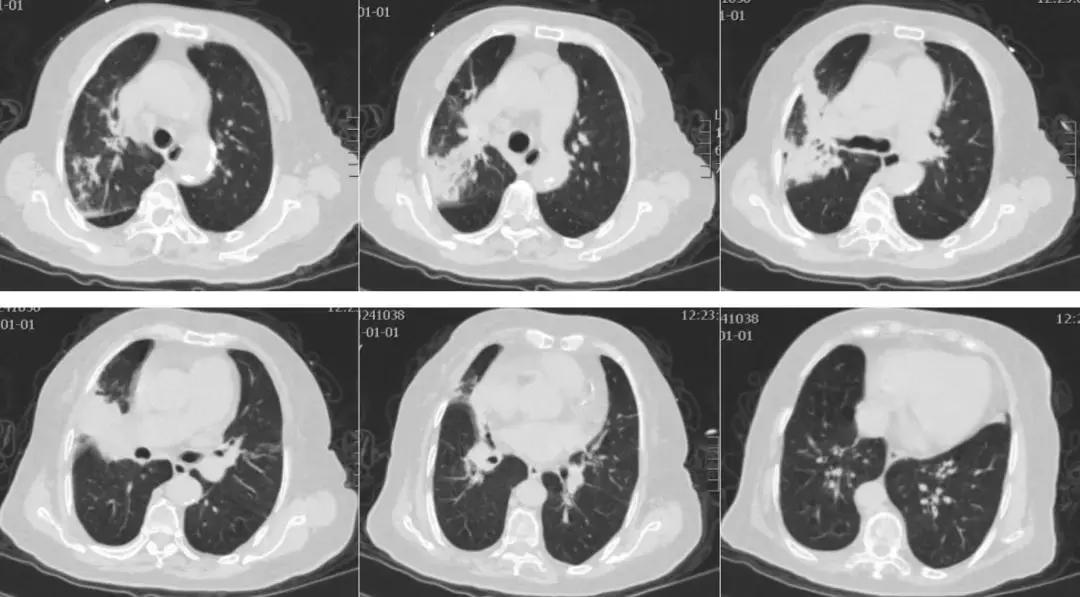

患者8年前无明显诱因出现晨起咳嗽、咳痰,咳白色粘痰,曾于当地医院诊断为「慢性支气管炎」,未系统治疗,无呼吸困难,入院前3天无明显诱因出现咳嗽加重,咳黄黏痰,量少,不易咳出,伴有发热,最高体温38.7℃,口服退热药物体温可降至正常。伴有呼吸困难,表现为反复发作性,剧烈咳嗽及活动后出现,于附近诊所给予抗感染、对症治疗(具体治疗方案不详),无明显好转,呼吸困难较前加重,为求进一步治疗来我院,急诊行胸部CT(见图1)检查提示右肺上叶、中叶支气管改变,双肺散在炎症改变,收入我科普通疗区。既往:发现高血压病史5年,血压最高180/90mmHg,间断口服拜新同,血压多控制于140/80mmHg;否认糖尿病、冠心病病史;否认吸烟、饮酒史。

【图1】入院前急诊胸部CT:右肺上叶、中叶支气管改变,双肺散在炎症改变